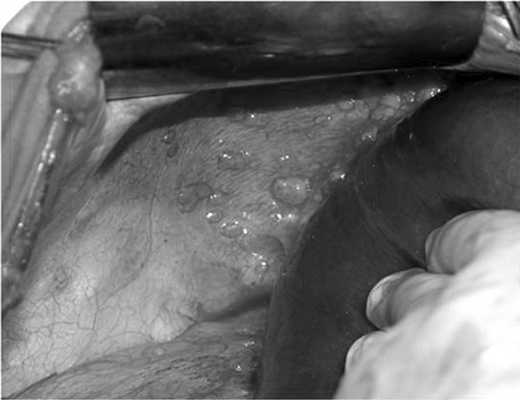

Клиническое наблюдение. Больная Т. в 2004 г. в возрасте 16 лет оперирована в РНЦРР с подозрением на опухоль яичников. При ревизии было выявлено поражение яичников, матки, тазовой брюшины, большого сальника. Произведена экстирпация матки с придатками, резекция большого сальника. При пересмотре стекол и ИГХ-исследовании установлен диагноз: злокачественная эпителиоидная мезотелиома. В послеоперационном периоде проведено 6 курсов ПХТ (гемзар/цисплатин, таксотер/цисплатин). В июне 2005 г. выявлено прогрессирование процесса. Больная обратилась в МНИОИ им. П.А. Герцена. При К.Т. выявлены опухолевые узлы на диафрагмальной поверхности брюшины справа до 1—3,5 см с прорастанием в ткань печени. В полости таза признаков рецидива не выявлено. Уровень СА125 в пределах нормы. 24.08.05 выполнена циторедуктивная перитонэктомия с удалением брюшины правого купола диафрагмы и правого латерального канала, атипичная резекция правой доли печени. Операция дополнена фотодинамической терапией (ФТД) брюшины с фотосенсибилизатором фотогем. В июне 2006 г. выполнена плановая флюоресцентная лапароскопия. При видеоревизии в режимах ауто- и аллофлюоресценции в нижних отделах передней брюшной стенки справа определяется несколько выбухающих очагов флюоресценции, при осмотре в белом свете рубцово-жировая ткань (рис. 1). Рис. 1. Очаги мезотелиомы на диафрагме. Проведен курс ФДТ брюшины с иссечением фрагмента измененной брюшины в зоне флюоресценции. При плановом гистологическом исследовании иссеченных фрагментов — инфильтративный рост эпителиодноклеточной мезотелиомы в фиброзно-жировой основе с эмболами в сосудах.